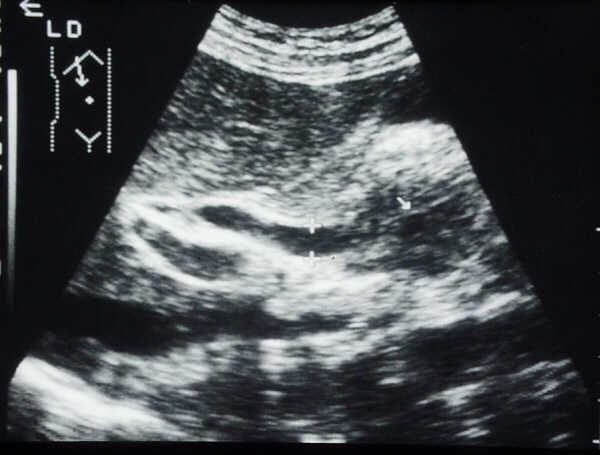

Oblique

subcostal scan with the patient in left lateral decubitus.

Dilated

(8 mm) common bile duct (between markers) in chronic pancreatitis with

enlarged, hypoechoic pancreatic head, with dilated Wirsung duct (arrow).